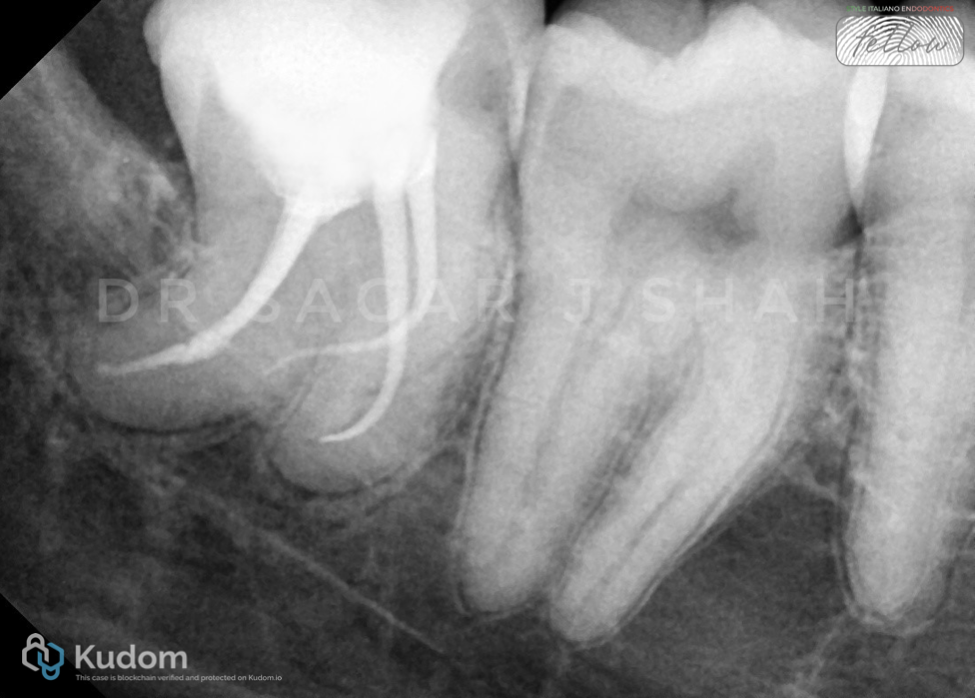

PREOPERATIVE ASSESSMENT:

Close proximity to the mandibular canal.

Pulp calcification was seen with the distal root.

AAE DIFFICULTY ASSESSMENT- HIGH